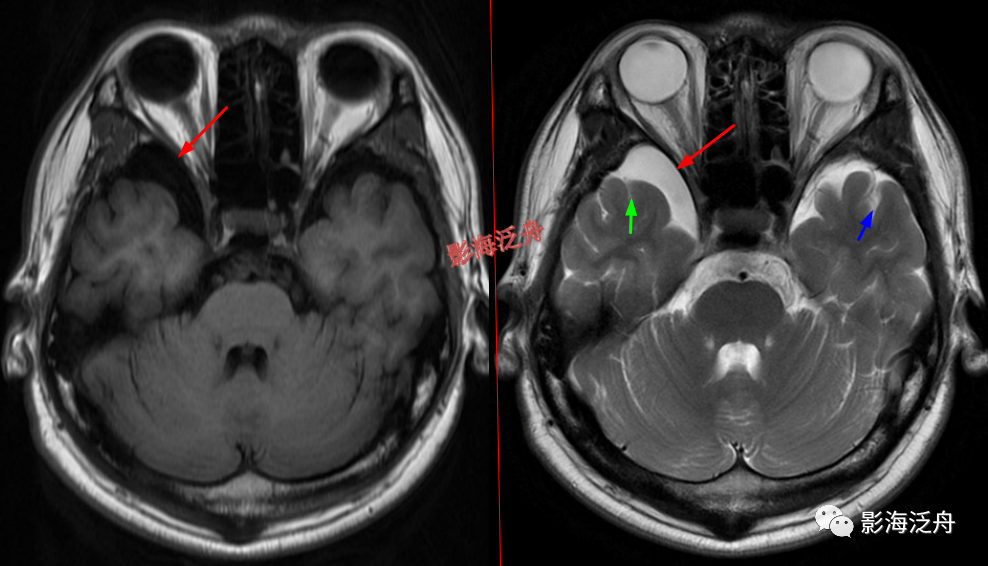

颞极前方蛛网膜囊肿(红箭)漏诊率也比较高,尤其在老年患者中,常常被误认为是扩大的蛛网膜下间隙,仔细观察可以发现右侧颞叶受压,脑沟闭塞(绿箭),与健侧(蓝箭)对比更为明显。

脑膜炎患者,桥前池内可见异常增多的血管影(红箭),正常人的桥前池因为脑脊液流动产生的伪影也可以看到池内絮状低信号(绿箭),但不如右侧患者的明显,这个观察起来比较困难,就如在腹部CT上观察患者是否存在肝脏肿大一样,需要一个经验积累的过程。黄箭指基底动脉,蓝箭指三叉神经。